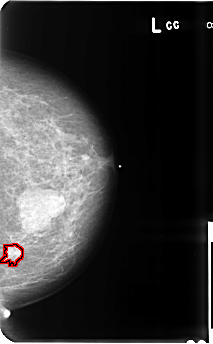

B_3512_1.LEFT_CC

LEFT_CC LINES 4816 PIXELS_PER_LINE 2976 BITS_PER_PIXEL 12 RESOLUTION 50 OVERLAY

FILE: B_3512_1.LEFT_CC.OVERLAY

TOTAL_ABNORMALITIES 1

ABNORMALITY 1

LESION_TYPE CALCIFICATION TYPE PLEOMORPHIC DISTRIBUTION CLUSTERED

LESION_TYPE MASS SHAPE IRREGULAR-ARCHITECTURAL_DISTORTION MARGINS SPICULATED

ASSESSMENT 5

SUBTLETY 4

PATHOLOGY MALIGNANT

TOTAL_OUTLINES 1

BOUNDARY